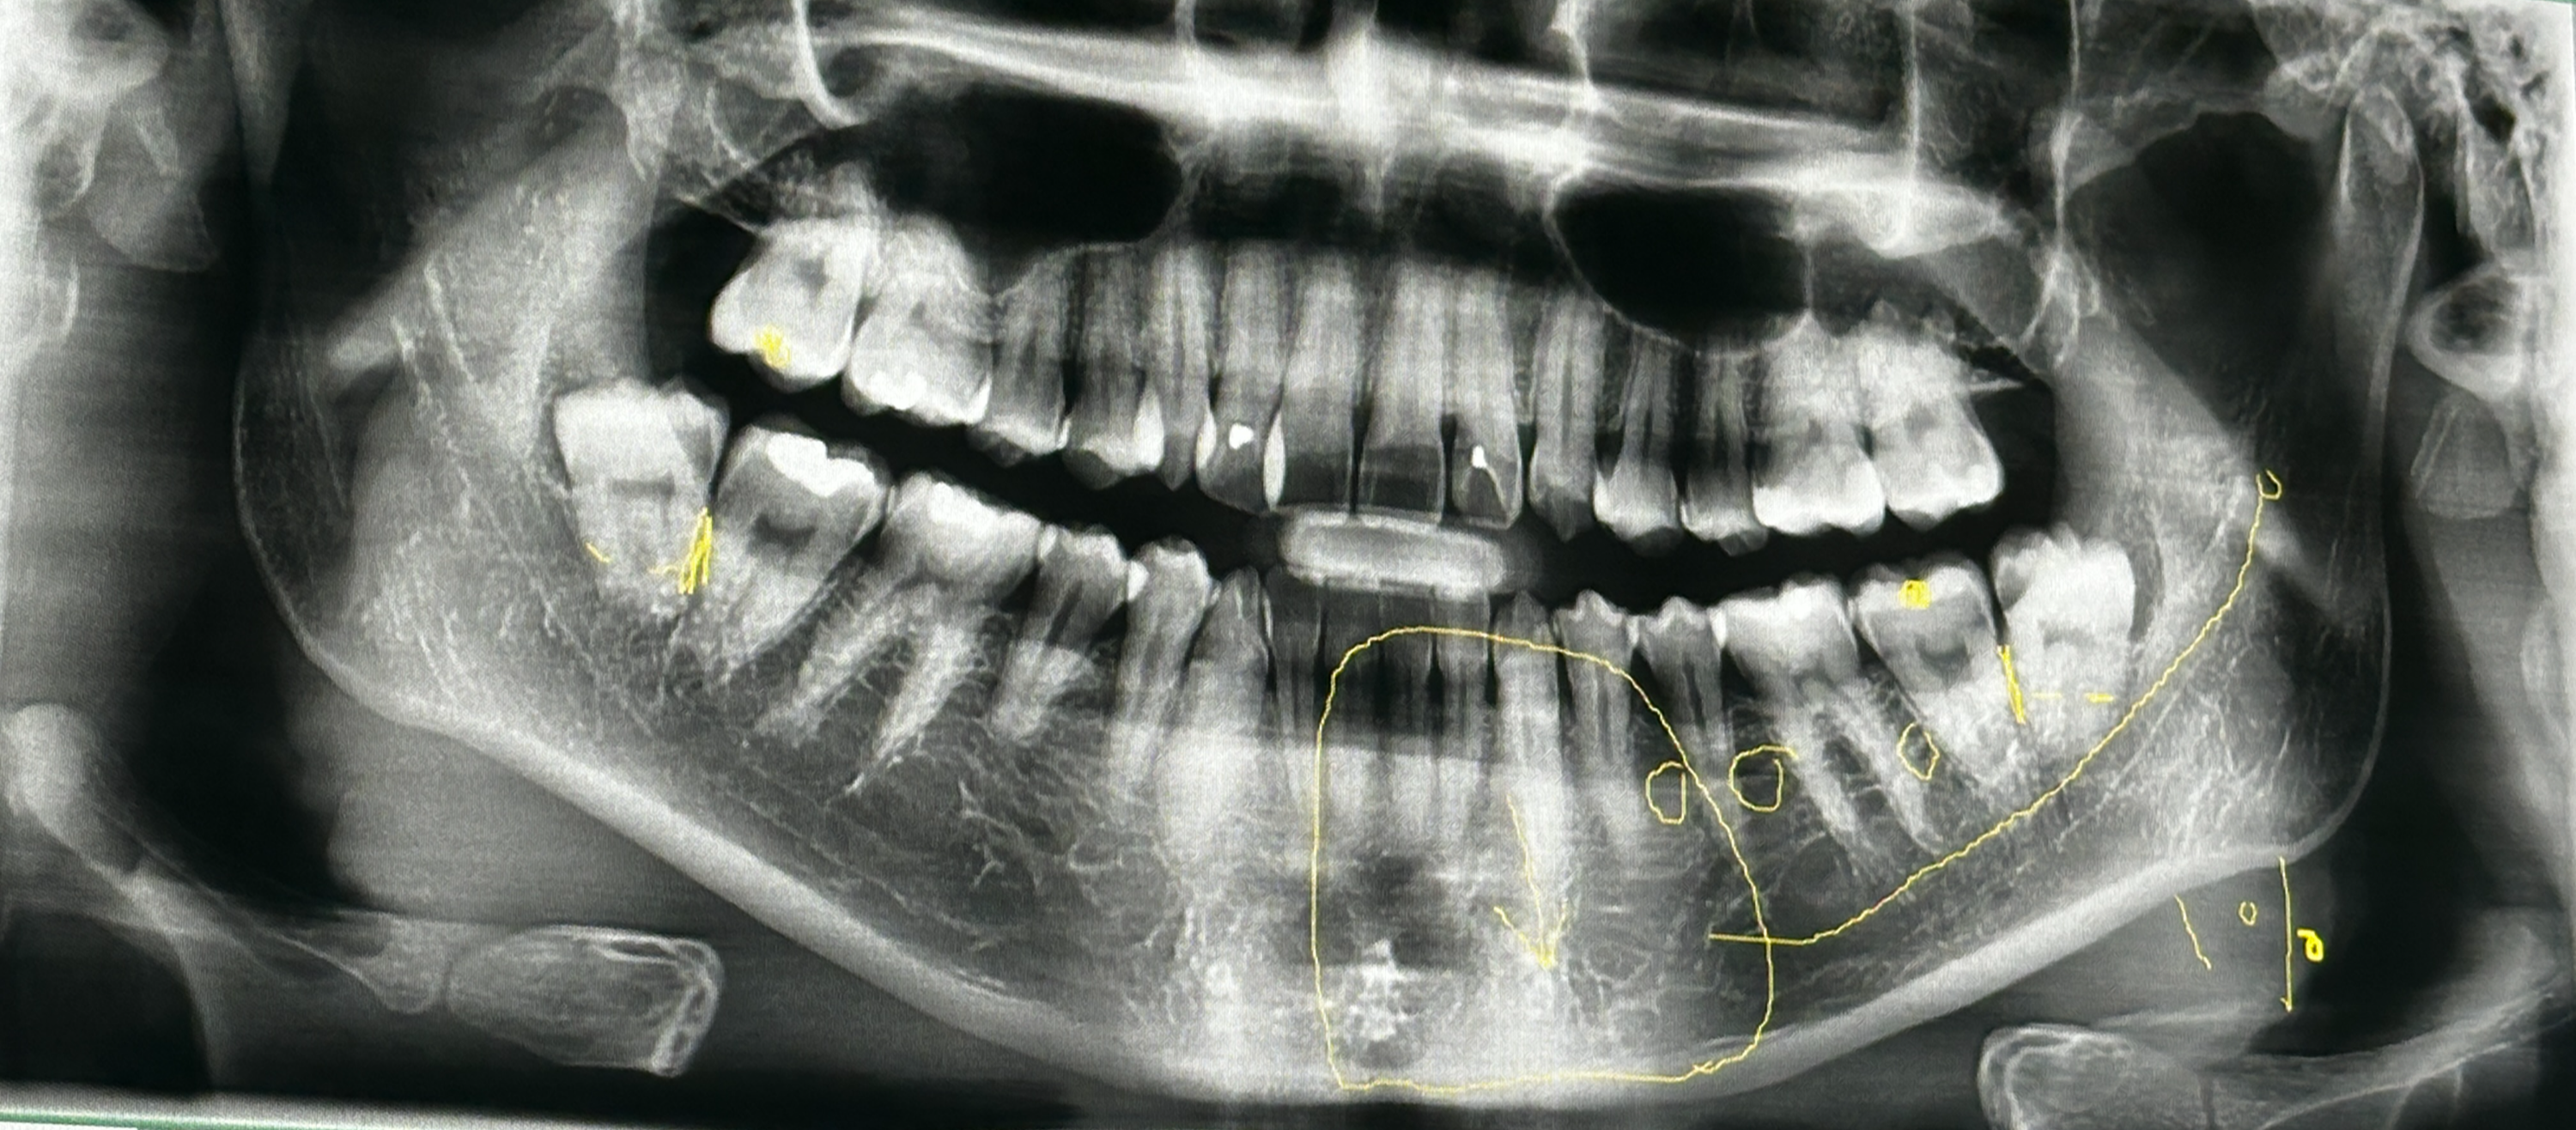

처음 가면 턱관절 CT를 찍어요. 이게 필수더라고요. CT 찍고 의사 선생님이 사랑니를 보시더니 "오늘 뽑을 수 있을 것 같네요"라고 하시는데... 사실 예전에 다른 병원에서 뺀찌당한 적이 있어서 좀 걱정했거든요? 근데 이 말 한마디에 왠지 안도감이 확 들더라구요.